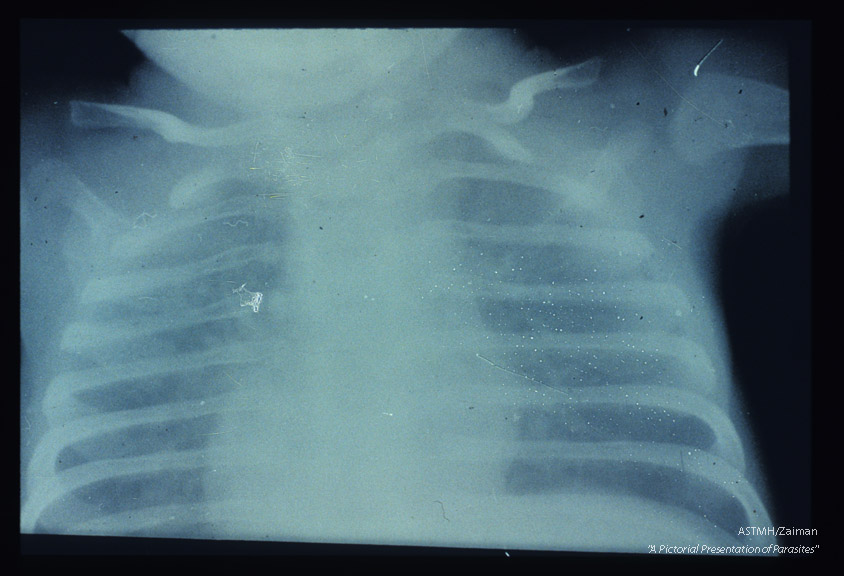

X-ray of child with pneumonia showing the characteristic ground glass appearance of such lungs.

Pneumocystis carinii

Description: X-ray of child with pneumonia showing the characteristic ground glass appearance of such lungs.